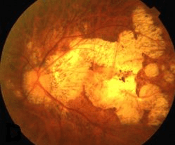

Media opacity: Cloudiness in the normally clear parts of the eye

The 2 parts of the eye responsible for focusing light are the cornea and the lens.

In some children, either the cornea or the lens can become cloudy and cause less light to be able to reach the back of the eye.